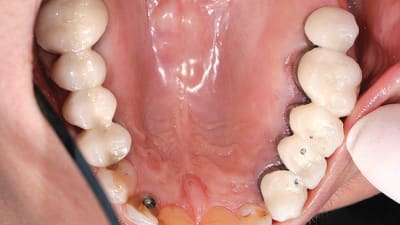

Continuing Education Surgical Considerations and Management in Mucocutaneous Disorders By Dan J. Holtzclaw, DDS, Nicholas D. Shumaker, DDS, Nicholas J. Toscano, DDS, Sean C. Meehan, DDS, Steven M. Stokes, DDS, Terry D. Rees, DDS June 01, 2010